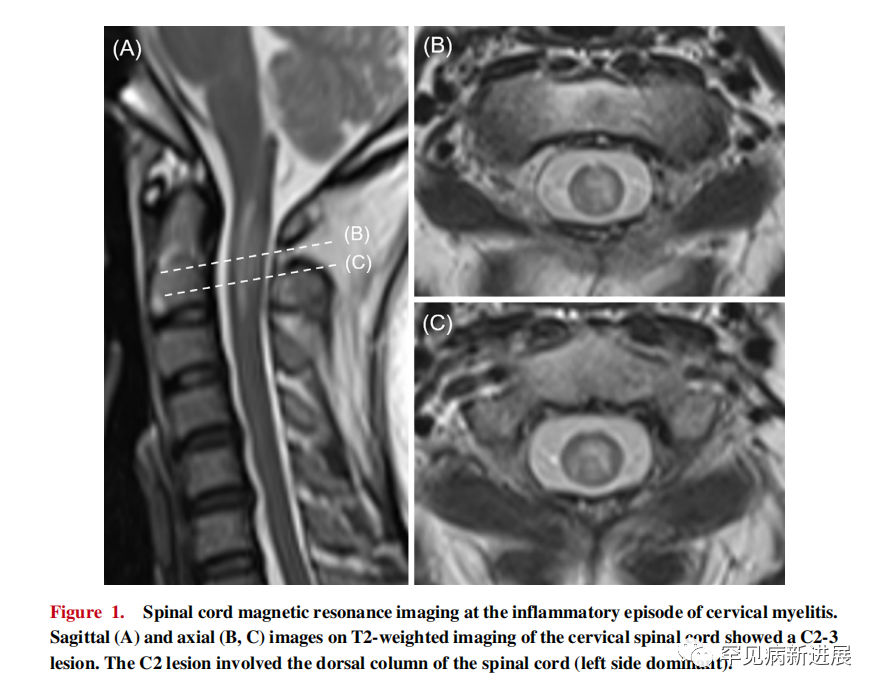

一名35岁的日本女性在3年内经历了5次炎症发作。在她32岁时,她出现了广泛的脊髓病变(Th2-7),并根据血清抗AQP4抗体阳性被诊断为NMOSD,33岁时,她出现了第三脑室病变和左侧视神经病变。34岁时,患者出现右侧视神经病变,C2-3颈椎病变累及脊髓背柱(图1)。在颈椎脊髓炎发作时,神经系统检查未发现虚弱,双侧上肢疼痛和振动感觉减弱,左颈部至左上肢有异位痛,还有尿功能障碍。在脊髓炎发作后大约一个月,她出现频繁的左上肢(每小时一次,视觉模拟评分10)疼痛性紧张性发作。 对于每次出现NMOSD复发,均给予急性静脉注射高剂量的甲基泼尼松龙和血浆置换治疗。尽管持续使用泼尼松龙(15-30 mg/day)和硫唑嘌呤(50-100mg/天)进行治疗,患者仍出现频繁复发。因此给予Satralizumab可预防未来 12 个月的复发(年化复发率从2.3至0次/年)。如上所述,患者在34岁的颈椎脊髓炎后出现左上肢疼痛性紧张性发作,给予卡马西平、氯硝西泮和加巴喷丁的治疗未能抑制这些癫痫发作。然而,Satralizumab单抗治疗显著缓解了她的疼痛性紧张性癫痫发作(包括疼痛的频率和程度),在Satralizumab治疗开始6个月后完全缓解(图2)。